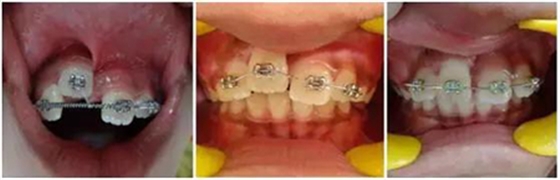

正畸牽引觀察其復(fù)位情況: 先觀察挫入的牙齒在未干預(yù)的情況下自發(fā)復(fù)位的情況。經(jīng)過(guò)3周的觀察,牙12復(fù)位,但牙11沒(méi)有顯示出復(fù)位的跡象。因此,使用MBT托槽正畸牽引牙11復(fù)位。為了讓其沿正確的方向復(fù)位,使用橡皮圈以獲得緩慢持續(xù)的牽引力(圖3)。

(圖3)

正畸牽引5周后,牙齒復(fù)位到其原始位置,與其他切牙完全對(duì)齊(圖3)。開(kāi)始嘗試血運(yùn)重建。重新打開(kāi)根管,使用次氯酸鈉和生理鹽水沖洗。然后插入無(wú)菌根管銼,并將其推到根尖處,以使血流進(jìn)入根管。一旦血液到達(dá)釉牙骨質(zhì)界,放置一個(gè)濕潤(rùn)的無(wú)菌棉球靜置15分鐘,直到血凝塊形成,再放置約2-3mm的MAT在血凝塊上。在MAT上覆蓋一個(gè)濕棉球,隨后進(jìn)行臨時(shí)修復(fù)。以后再替換為玻璃離子水門(mén)汀墊底和復(fù)合樹(shù)脂修復(fù)。復(fù)診時(shí)間為1、3、6、9和12月。正畸復(fù)位保留12周。然而,在這么長(zhǎng)的保留期內(nèi)還是復(fù)發(fā)了錯(cuò)位,這也強(qiáng)調(diào)了在嚴(yán)重侵入的情況下長(zhǎng)期復(fù)位的重要性,因?yàn)槔奂暗难例X周圍出現(xiàn)大量的牙槽骨喪失(圖 4)。